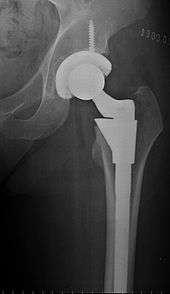

Hip replacement is a surgical procedure in which the hip joint is replaced by a prosthetic implant. Hip replacement surgery can be performed as a total replacement or a hemi (half) replacement. Such joint replacement orthopaedic surgery is generally conducted to relieve arthritis pain or in some hip fractures. A total hip replacement (total hip arthroplasty) consists of replacing both the acetabulum and the femoral head while hemiarthroplasty generally only replaces the femoral head. Hip replacement is currently the most common orthopaedic operation, though patient satisfaction short- and long-term varies widely. The average cost of a total hip replacement in 2012 was $40,364 in the United States, and about $7,700 to $12,000 in most European countries.[1]